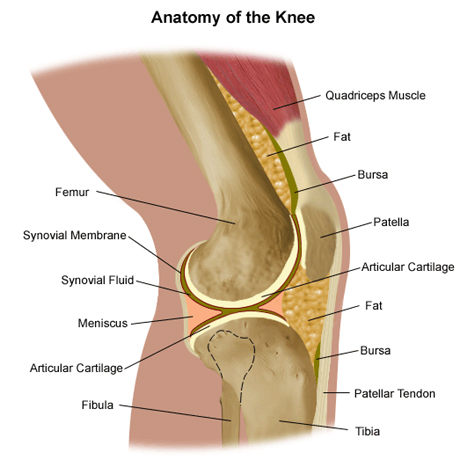

Anatomy of the knee

Joint consist of an area involving motion between two joint surfaces. Most joints are mobile, allowing the bones to move. Basically, the knee is 2 long leg bones held together by muscles, ligaments, and tendons. Each bone end is covered with a layer of cartilage that absorbs shock and protects the knee.

The knee consists of the following:

- Tibia. This is the shin bone or larger bone of the lower leg.

- Femur. This is the thighbone or upper leg bone.

- Patella. This is the kneecap.

- Cartilage. A type of tissue that covers the surface of a bone at a joint. Cartilage helps reduce the friction of movement within a joint.

- Synovial membrane. A tissue that lines the joint and seals it into a joint capsule. The synovial membrane secretes synovial fluid (a clear, sticky fluid) around the joint to lubricate it.

- Ligament. A type of tough, elastic connective tissue that surrounds the joint to give support and limits the joint’s movement.

- Tendon. A type of tough connective tissue that connects muscles to bones and helps to control movement of the joint.

- Meniscus. A curved part of cartilage in the knees and other joints that acts as a shock absorber, increases contact area, and deepens the knee joint.

Normal knee anatomy.